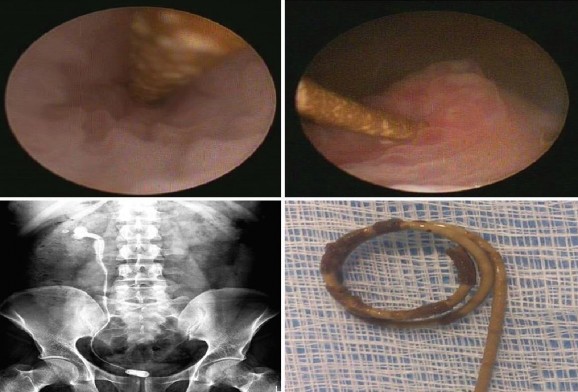

Vôi hóa ống thông niệu quản JJ

Các yếu tố khác nhau như nước tiểu quá bão hòa, mang thai, mang ống thông niệu quản thời gian dài… làm tăng nguy cơ vôi hóa bề mặt thông niệu quản [116].

Theo báo cáo của el-Faqih S.R. và cs (1991) [50] thì tỷ lệ vôi hóa ống thông niệu quản là 9,2% (đặt < 6 tuần), 47% (đặt 6 – 12 tuần) và khoảng 76,3% (đặt > 12 tuần). Theo báo cáo khác của tác giả Kawahara T. và cs (2012) [89] thì tỷ lệ vôi hóa ống thông niệu quản là 26,8% (< 6 tuần), 56,9% (6 -12 tuần) và khoảng 75,9% ( > 12 tuần). Sự vôi hóa có thể gặp ở đầu xa của ống thông nằm trong bàng quang, dọc theo chiều dài ống thông nằm trong niệu quản hoặc đầu gần của thông trong bể thận.

Hình 1.14. Ống thông niệu quản JJ vôi hóa trên phim hệ tiết niệu không chuẩn bị và nội soi bàng quang

(Nguồn: Aboutaleb HA, 2019) [15]